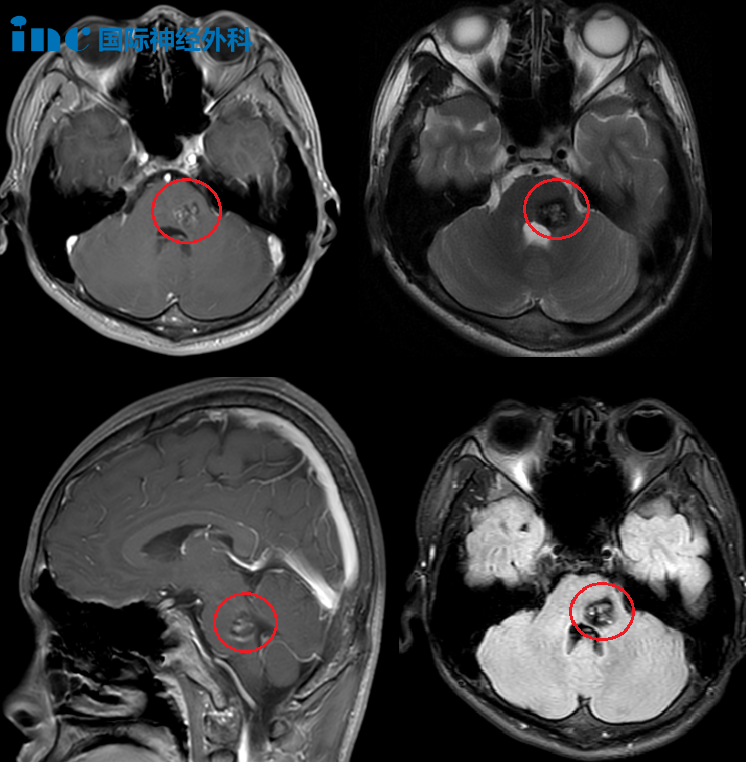

2024年2月,正全力备战中考体育测试的小波突然出现右腿麻木,很快蔓延至整个右半身。核磁共振结果显示:脑干海绵状血管瘤并出血。这不是肿瘤,而是一团脆弱的异常血管,随时可能破裂。更危险的是,它长在控制呼吸、心跳的“生命中枢”——脑干。

▼病灶位于桥脑左侧,并且与桥臂的交界处,病灶大,位置深。